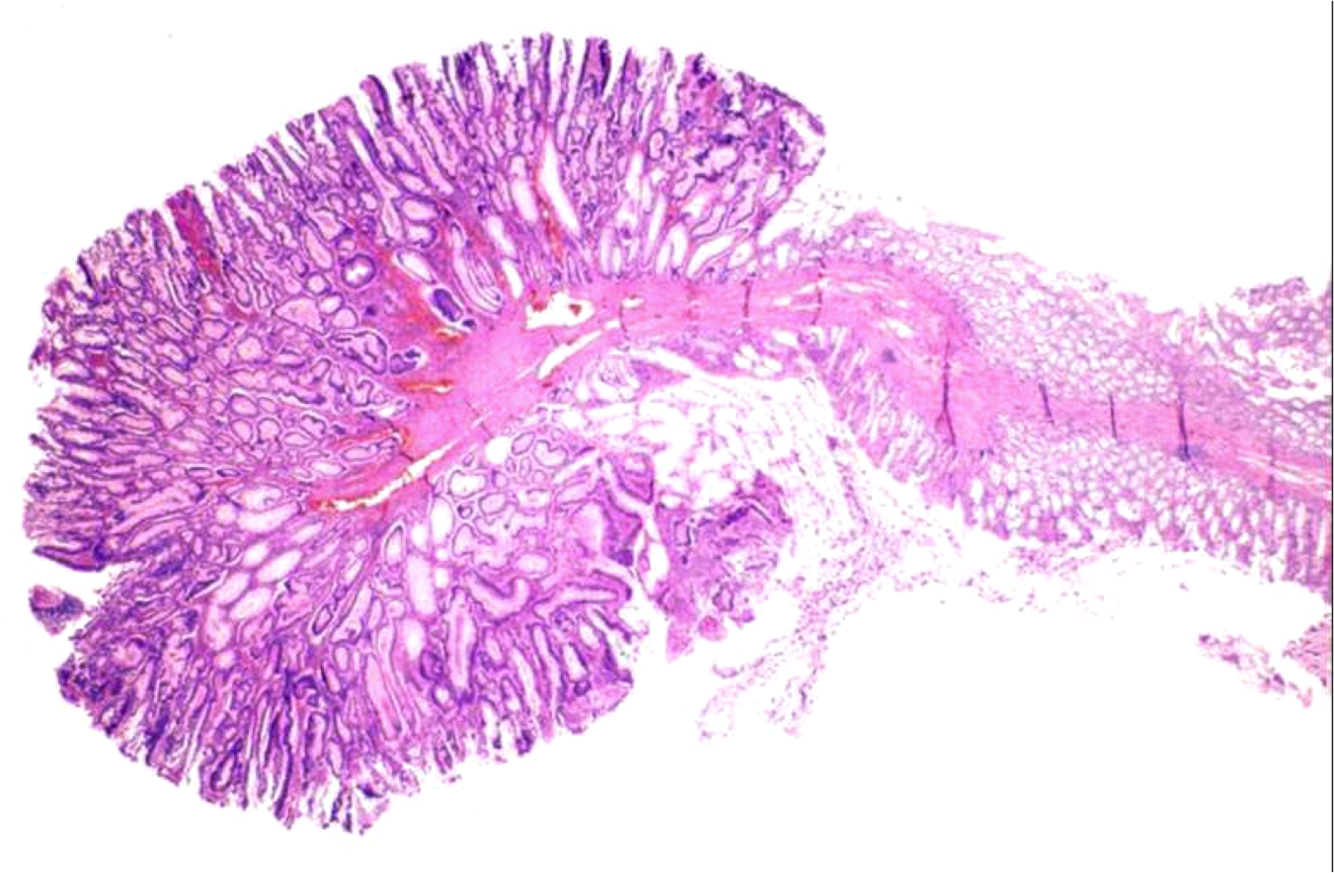

Adenoma of Colon:

Most colon cancers arise from what?

Adenoma of colon- always pre-malignant, but good to find because they can be removed before they become malignant

How can you tell if Adenoma of Colon has invaded?

Stromal desmoplasia

Familial Adenomatous Polyposis